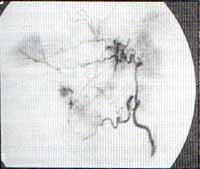

La embolización en 6 casos se hizo usando técnica selectiva y sólo en 2 fue supraselectiva. Las figuras 1,2,3,4 ,muestran algunos casos de la serie, antes y después de la embolización.

Figura 3. Paciente de sexo masculino, de 50 años, con hemoptisis masiva por TBC activa en lóbulo superior derecho. (a) Arteriografía bronquial derecha, muestra dilatación y tortuosidad de las ramas bronquiales, como signo indirecto de sangrado. (b) Control de embolización con partículas de gelfoam + alcohol absoluto, con oclusión total de la arteria y remisión de la hemoptisis.

Figura 4. Paciente de sexo femenino, de 32 años, con hemoptisis por aspergiloma. (a) Arteriografía de la arteria subclavia izquierda, que muestra opacificación de las ramas torácicas superiores, con extravasación del medio de contraste, hipertrofia y tortuosidad de las ramas distales. (b) Control de embolización supraselectiva con gelfoam + alcohol absoluto, a través de microcatéter y colocación de Coils en el orígen de la arteria torácica superior, con remisión total de la sintomatología.